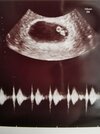

Hej! U mnie sytuacja ma się tak że według USG 7tydz plius 5 dni a według @ powinno być już koło 9tyg więc coś się musiało poprzesuwać....według lekarza wszystko ok tylko zaś był problem z USG nawet na lepszym sprzęcie widoczność na USG dopochwowym bardzo słaba prawdopodobnie przez zrosty po CC i też słabo było wychwycić tętno ale mój gin twierdzi że widzi ruch zarodków i że wykrylo przepływ krwi więc serduszka też powinny być na miejscach tylko tak jak mi to powiedział to ciąża młodsza drugi fakt bliźniaki i za dwa tygodnie kolejna wizyta i żebym była spokojna jak to on to stwierdził ciąża się trzyma może już pani się ujawnić he ( apropo moja mama położna pracuje z tym lekarzem w szpitalu) odnośnie tego ujawniania się😂

Piekne widac na usg 💪 . Zawsze wychodzą jakieś niewielkie różnice dni między miesiączką a usg . Mi samej wyszla różnica 2 ,3 dni - ale najważniejsze ze lekarz nie widzi nic niepokojącego 💪. No to już wiemy kto będzie miał największy brzuszek na forum 🤣❤️

Jest serduszko! ♥️ Zarodek ma 8mm a w zeszła sobotę pęcherzyk miał tylko 3mm. Dzisiaj 6+5 termin na 12.02. Jakbym mogła cofnąć czas nie szłabym na wizyte przed końcem szóstego tygodnia. Im mniej wiesz tym lepiej śpisz.

Ale ekstra, pięknie wyglądają te dwa pecherzyki 🥰🥰